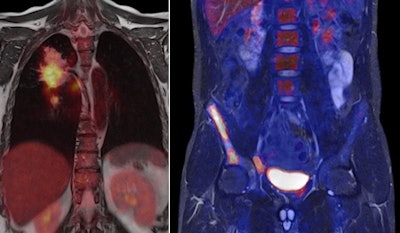

With simultaneous acquisition by both modalities, a fused dataset is available automatically, but, at the same time, both datasets can be viewed separately. "For the first time, it is possible to do an assessment of oncologic disease in the head and brain, and the whole body," Maerzendorfer said.

| PET/MRI images courtesy of Siemens Healthcare. |

Maerzendorfer also mentioned Biograph mMR's use with both current and future PET tracers. "The classical PET tracers that are available today can combine the outstanding soft-tissue contrast of MR with the physiological function and capabilities of PET," he said. "We also see neurodegenerative diseases as another field. I would also mention pediatric applications, where CT is not used on children to reduce their exposure levels to radiation."